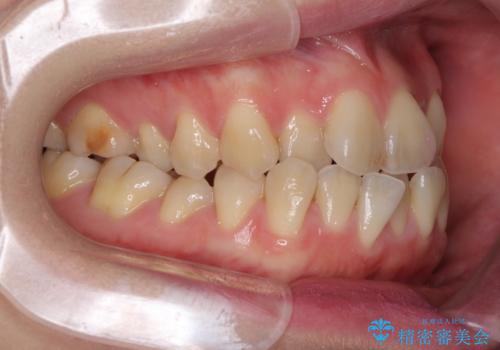

ハーフリンガル 反対咬合の改善

目立ちにくい装置での治療をご希望とのことで、上顎が裏側装置、下顎が表側装置のハーフリンガルにより矯正治療を行うこととしました。

下顎の歯列全体を後方に動かす場合、さまざまリスクを伴うため慎重に行う必要があり、さらには移動量に限界があるため、治療計画は無理のないものとしなければなりません。

下顎左右の奥にアンカーボルトを使用して、無理のない範囲で後方に移動させ、きれいに仕上げることができました。